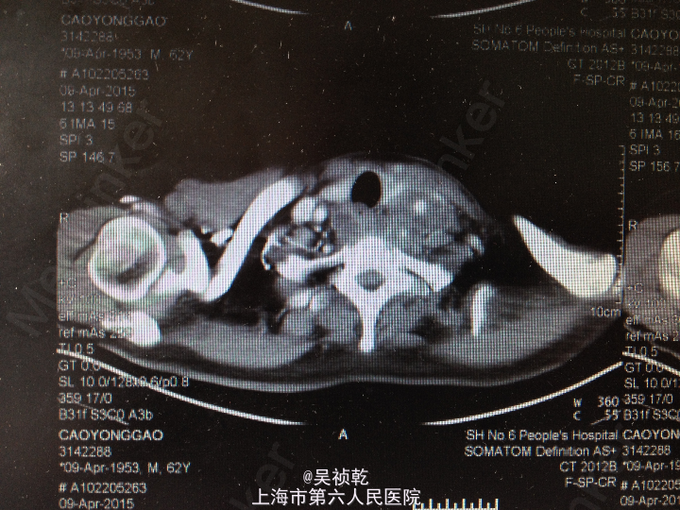

查体:神志清醒,呼吸稍促,推入病房,发育正常,营养良好,自主体位。皮肤粘膜:无黄染,无瘀点瘀斑,无贫血貌,无肝掌,无蜘蛛痣。淋巴结:全身浅表淋巴结可触及肿大。双侧颌下淋巴结肿大,左侧颈部肿大,皮肤红肿,皮温偏高,局部有波动感。头颈部:无头颅畸形,无巩膜黄染,无结膜苍白 ,口唇无紫绀,无扁桃体肿大。颈软,气管居中,甲状腺无肿大,无颈静脉怒张。胸部:胸廓无畸形,心率105次/分, 节律齐,无杂音,两肺呼吸音清,未及啰音。腹部:腹部平坦,腹壁柔软,全腹无压痛、无反跳痛,肝脏肋下未触及,脾肋下未触及,肝区无叩击痛,肾区无叩击痛。无移动性浊音,肠鸣音正常。肛门、直肠及外生殖器: 正常。脊柱与四肢:脊柱无畸形,四肢无畸形,四肢活动自如。神经系统:生理反射存在,病理反射未引出。 辅检:2015-4-8 血气检验报告:二氧化碳分压 34.7 mmHg ↓,氧分压 60.9 mmHg ↓,氧饱和度 91.8 % ↓。门诊化验检验报告:凝血酶原时间 13.1 秒 ,国际标准化比率 1.19 ↑,部分凝血活酶时间 30.4 秒 ,D二聚体 1.13 mg/L FEU ↑,纤维蛋白(原)降解产物 6.4 mg/L ↑。 生化检验报告:肌钙蛋白-I 0.013 ,CKMB 1.4 ug/L ,肌红蛋白 28.6 ug/L 。 生化检验报告:血清钾(干式) 4.5 mmol/L ,血清钠(干式) 137 mmol/L ↓,血清氯(干式) 94 mmol/L ↓,总蛋白(干式) 66 g/L ,白蛋白(干式) 32 g/L ↓,谷丙转氨酶(干式) 26 U/L ,谷草转氨酶(干式) 16 U/L ,γ-谷氨酰酶(干式) 19 U/L ,碱性磷酸酶(干式) 103 U/L ,总胆红素(干式) 16 μmol/L ,尿素(干式) 7.5 mmol/L ↑,肌酐(干式) 67 μmol/L ,尿酸(干式) 154 μmol/L ↓,淀粉酶(干式) <30 U/L ↓,血糖(干式) 22.0 mmol/L ↑,B型钠尿肽前体(proBNP) 199.80 ng/L ↑。 2015-4-9 血常规检验报告:白细胞 13.2 X10^9/L ↑,红细胞 3.76 X10^12/L ↓,血红蛋白 125 g/L ↓,细胞比积 35.8 % ↓,血小板 261 X10^9/L ,淋巴细胞百分比 4.7 % ↓,中性细胞百分比 84.4 % ↑。糖尿病医学中心检验报告:糖化血红蛋白 12.40 % ↑。 颈部超声示:双侧颌下淋巴结肿大,左侧颈后软组织结构紊乱,内混合回声及肿大淋巴结,考虑炎性改变可能,建议治疗后复查。 颈部CT:1.咽后间隙、左侧咽旁间隙及颈动脉鞘软组织明显肿胀、渗出,颈部多发肿大淋巴结,考虑炎症可能大,请结合临床并门诊增强CT评估。2.左侧甲状腺小结节可能,请结合临床,必要时随访。 2015-4-9 颈部增强CT示:颈部及胸腔纵隔脓肿形成。 2015-4-8引流分泌物培养结果: 肺炎克雷伯菌。

患者入院时诊断为:1.左颈部脓肿,颈部软组织感染,纵膈脓肿形成。2.糖尿病。 入院后予对症处理:1.加强抗感染,予万古霉素+磷霉素联合。2.床边行脓肿切开引流,引流液送培养。2、予吸氧、禁食、营养支持等对症治疗。3.病情危重,告知家属相关风险,予告病危。4.进一步完善颈部及胸部增强CT,病请五官科会诊。 2015.04.09CT提示颈部,咽后壁及胸腔纵隔脓肿形成,故请五官科及胸外科会诊,会诊意见为:手术切开引流。故于4.9全麻下行颈部脓肿清创引流术。 手术过程:患者取仰卧位,肩部垫高,全麻达成后,常规消毒铺巾。在胸骨切迹上约两横指处顺皮纹方向作弧形领式切口,长约8cm。依次切开皮肤、皮下组织和颈阔肌。游离颈阔肌深面间隙,在其深面用电刀分离皮瓣,上至甲状软骨切迹,下至胸骨切迹,两侧越过胸锁乳突肌前缘。分离右侧胸锁乳突肌,分离至咽后间隙,咽后间隙内见大量脓液,予双氧水,稀碘伏水,及生理盐水彻底冲洗脓腔。术中请胸外科会诊认为目前上纵隔脓肿暂无需处理。左右各置一根颈部引流管;仔细止血;清点器械无误后,缝合皮下及皮肤层。术中出血少未输血,术程顺利,病人安返。 术后诊断:1.左颈部脓肿,颈部软组织感染,纵膈脓肿形成。2.糖尿病。3.全身感染症状。4.吞咽困难。 术后结合药敏结果,继续予万古霉素+磷霉素联合抗炎,引流管予生理盐水持续冲洗引流,目前引流液不多,术后一周复查CT见脓肿明显缩小,纵膈脓肿有所缩小,目前治疗方案:1.停用原抗菌方案,换用莫比沙星 0.4 qd 静滴,每次滴注90min;2.每3天复查血象,及时复查颈部CT,治疗5天后再评估,一般情况好可停药随访;3.糖尿病患者,注意血糖变化,监测心功能及肝肾功能。